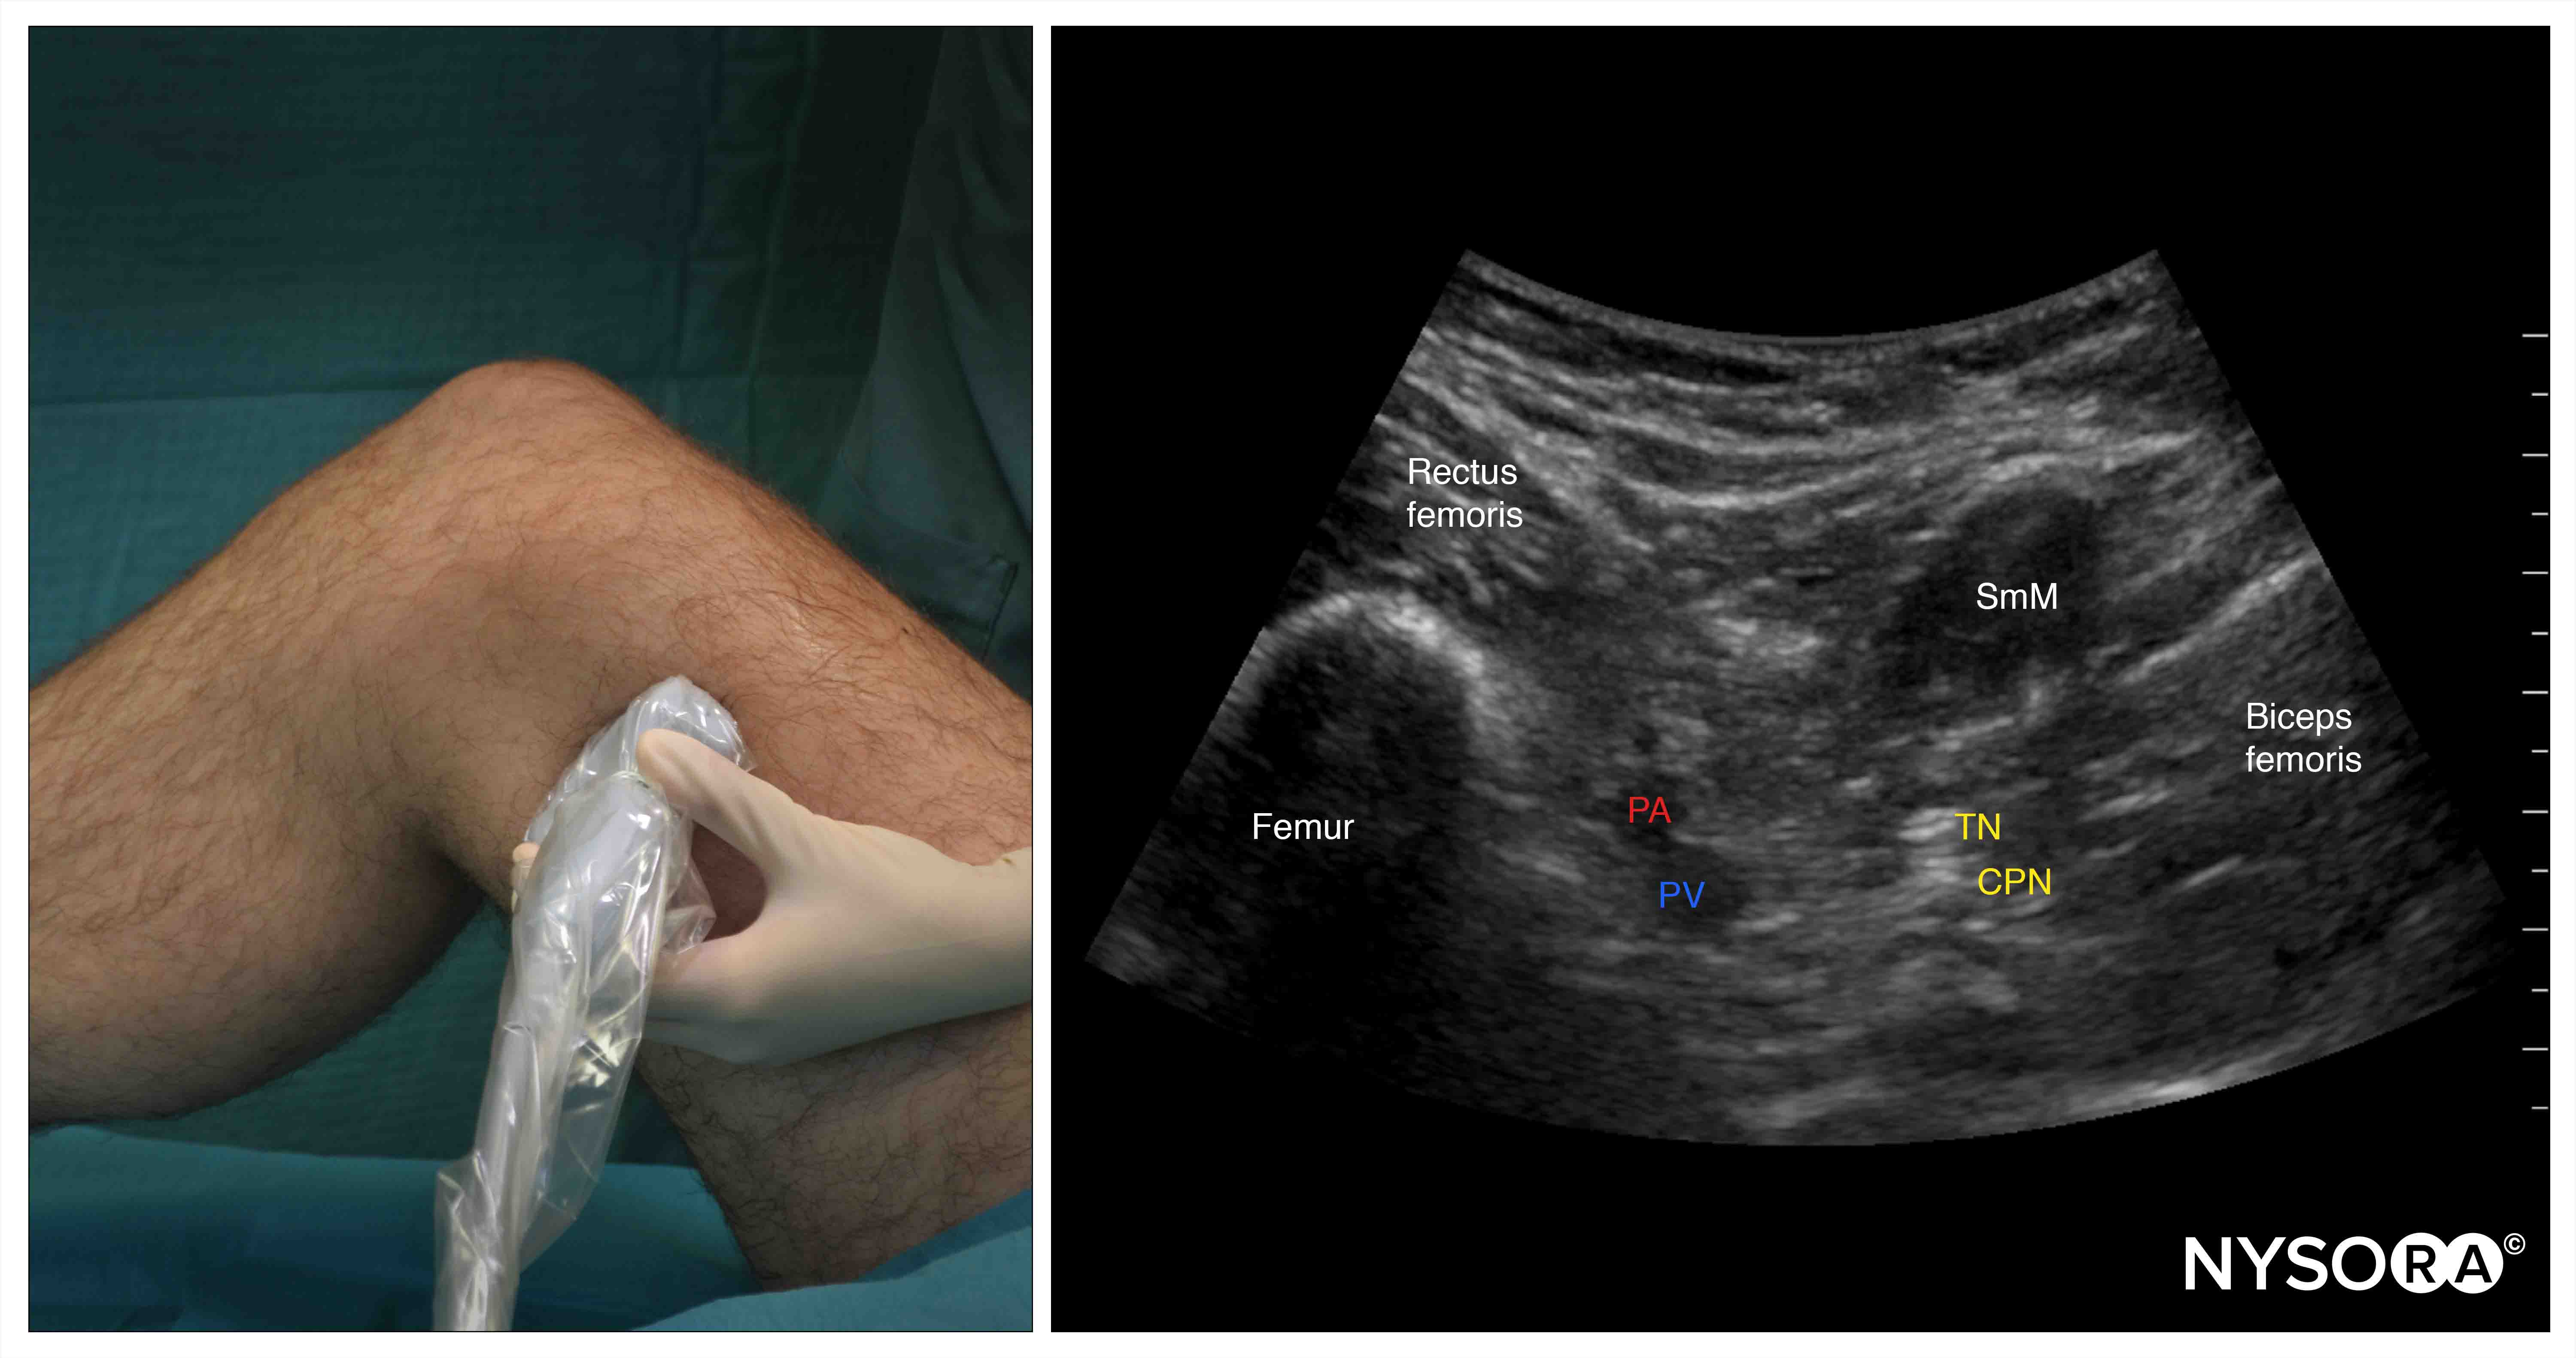

2 medical university of south carolina, charleston, sc, 29425, usa. Regional anaesthesia for knee surgery: This block shows an animated regional radar image.